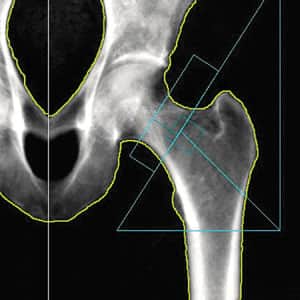

Bone densitometry, also known as DEXA scan (Dual Energy X-ray Absorptiometry), involves the use of a small dose of ionizing radiation to generate images of the interior of the body, typically focusing on the lower spine and hips to measure bone density. It is a widely utilized method for diagnosing osteoporosis due to its speed, non-invasiveness, and simplicity.

According to the World Health Organization, DEXA scan is considered the best technique for assessing bone mineral density in postmenopausal women. It is also commonly referred to as DXA or bone densitometry. This imaging procedure plays a crucial role in evaluating bone health and diagnosing conditions like osteoporosis.